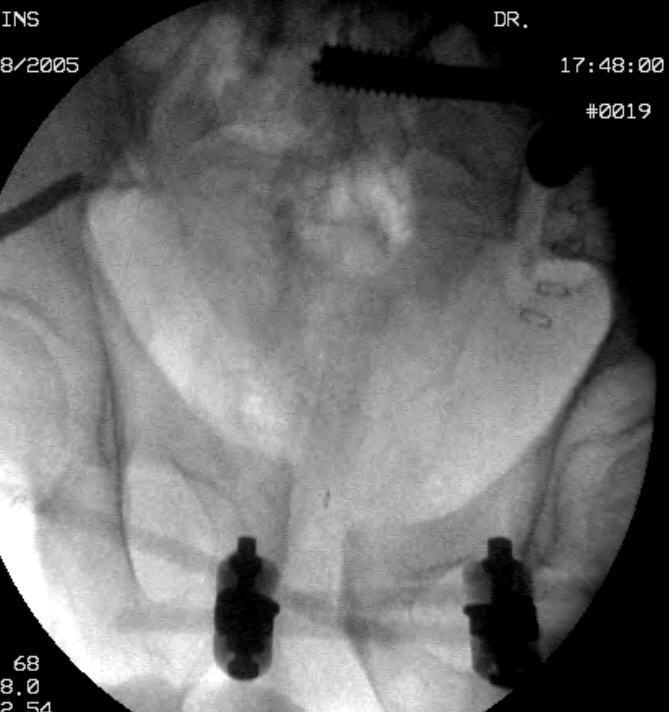

Hello gentlemen- Case is 52 YO male, fell out of treestand while deerhunting. He is 6 ft, approx. 260-275 lbs. Was hemodynamic unstable at local ER, sent to our Trauma center where circumferential pelvic binder placed and pt. stabilized with fluid, blood, and rewarming. Angiography not performed. An extraperitoneal bladder disruption was found, uro elected to treat non-operatively. Initial xray (not shown) demonstrated 5-7 cm wide at symphysis and SI joint. The first image attached is of CT once binder is in place. On post trauma day 5 the pt was taken to OR for ORIF of his iliac wing fracture and SI dislocation. The swelling/3rd spacing of fluid in the area of symphysis was profound, but quite acceptable posteriorly. Patient was prone for procedure, as I thought too difficult to fix the wing in lateral position. Of course the repair of wing was easy, but reduction of SI very demanding. The Floro images document the residual lack of reduction. That was the closest I could get it using 6mm joystick in wing, and clamp on sacrum and clamp through notch. The fixation was (initially) rigid. Anterior ex fix with supra-acetabular pins was placed due to condition of soft tissues, massive "beer-belly" overhanging the crest. Post trauma day ten patient's xray shows failure of posterior construct. Plan was to perform revision orif once soft tissues resolve considerably for full anrterior fixation and posterior fixation. However, while Im away for holiday (on Post trauma day 15), pt is developing septic clinical appearance, and trauma suspects pelvic abcess near symphysis and performs I and D - finds nothing but no primary closure performed. Posterior tissues/incision continue to look healthy. Now is post trauma day 17, pt is still tubed/on dopamine/and wbc still elevated, anterior incision still packed open. Clearly must get to bottom of possible sepsis, but then what? Thanks for you time - sorry for such lengthy clinical description. Thomas Schaller Kalamazoo, Michigan

5. Your caudal iliosacral screw is/was in his spinal canal... it's low and posterior and the lateral fluoro image confirms this... a postop CT will show it (or it's trail at this point)... canal screws do not hold.